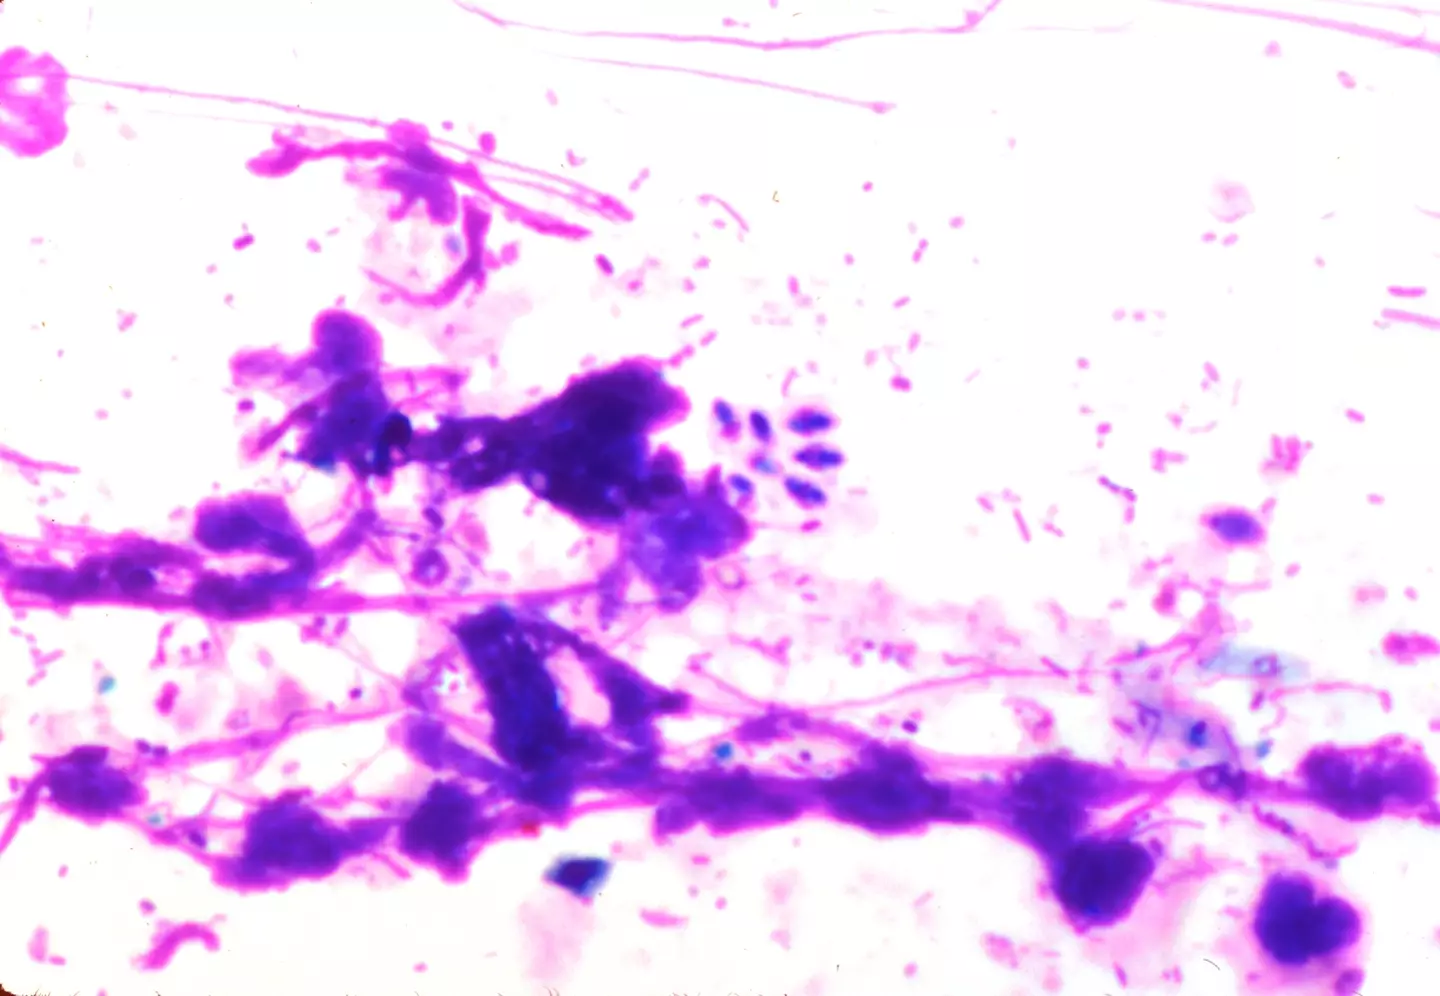

The toxin is called Toxoplasma gondii – also known as T. gondii, and can enter the body by eating undercooked meat or through exposure to cat feces.

In a paper published in PLoS Pathogens, scientists explained how the parasite can interfere with brain cells by infecting a number of neurons.